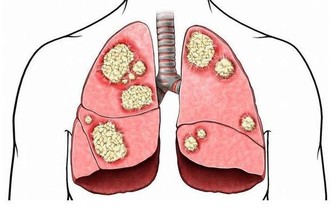

體重迅速下降且伴隨著打嗝,是腸道阻塞的標誌。如果你本來不打算減肥,體重卻在快速下降,則可能意味著你的身體沒有正確地消化你所吃的食物,醫生可能會檢查你是否患有如腸易激綜合徵、食物過敏或克羅恩病在內的疾病。另外,打嗝與體重下降同時出現,也很可能是胃癌的徵兆。